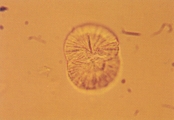

Кальция карбонат может кристаллизоваться в моче лошадей, кроликов, коз, образуя большие желто-коричневые или бесцветные сфероиды с радиальной исчерченностью, или маленькие кристаллы круглой, овальной или гантелеобразной формы (рис. 2 и 3). У собак и кошек эти кристаллы обычно не обнаруживаются. Если в моче обнаруживается гантелеобразный кристалл, то это скорее кальция оксалат моногидрат.

Рис. 2. Микрофотография кристаллов кальция карбоната в мочевом осадке 7-летней кобылы (не окрашено, увеличение Х160

КАЛЬЦИЙ КАРБОНАТНАЯ КРИСТАЛЛУРИЯ